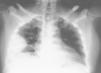

Varón de 63 años con hemoptisis, dolor pleurítico y masa pulmonar

A 63-year-old male with hemoptysis, pleuritic pain, and lung mass